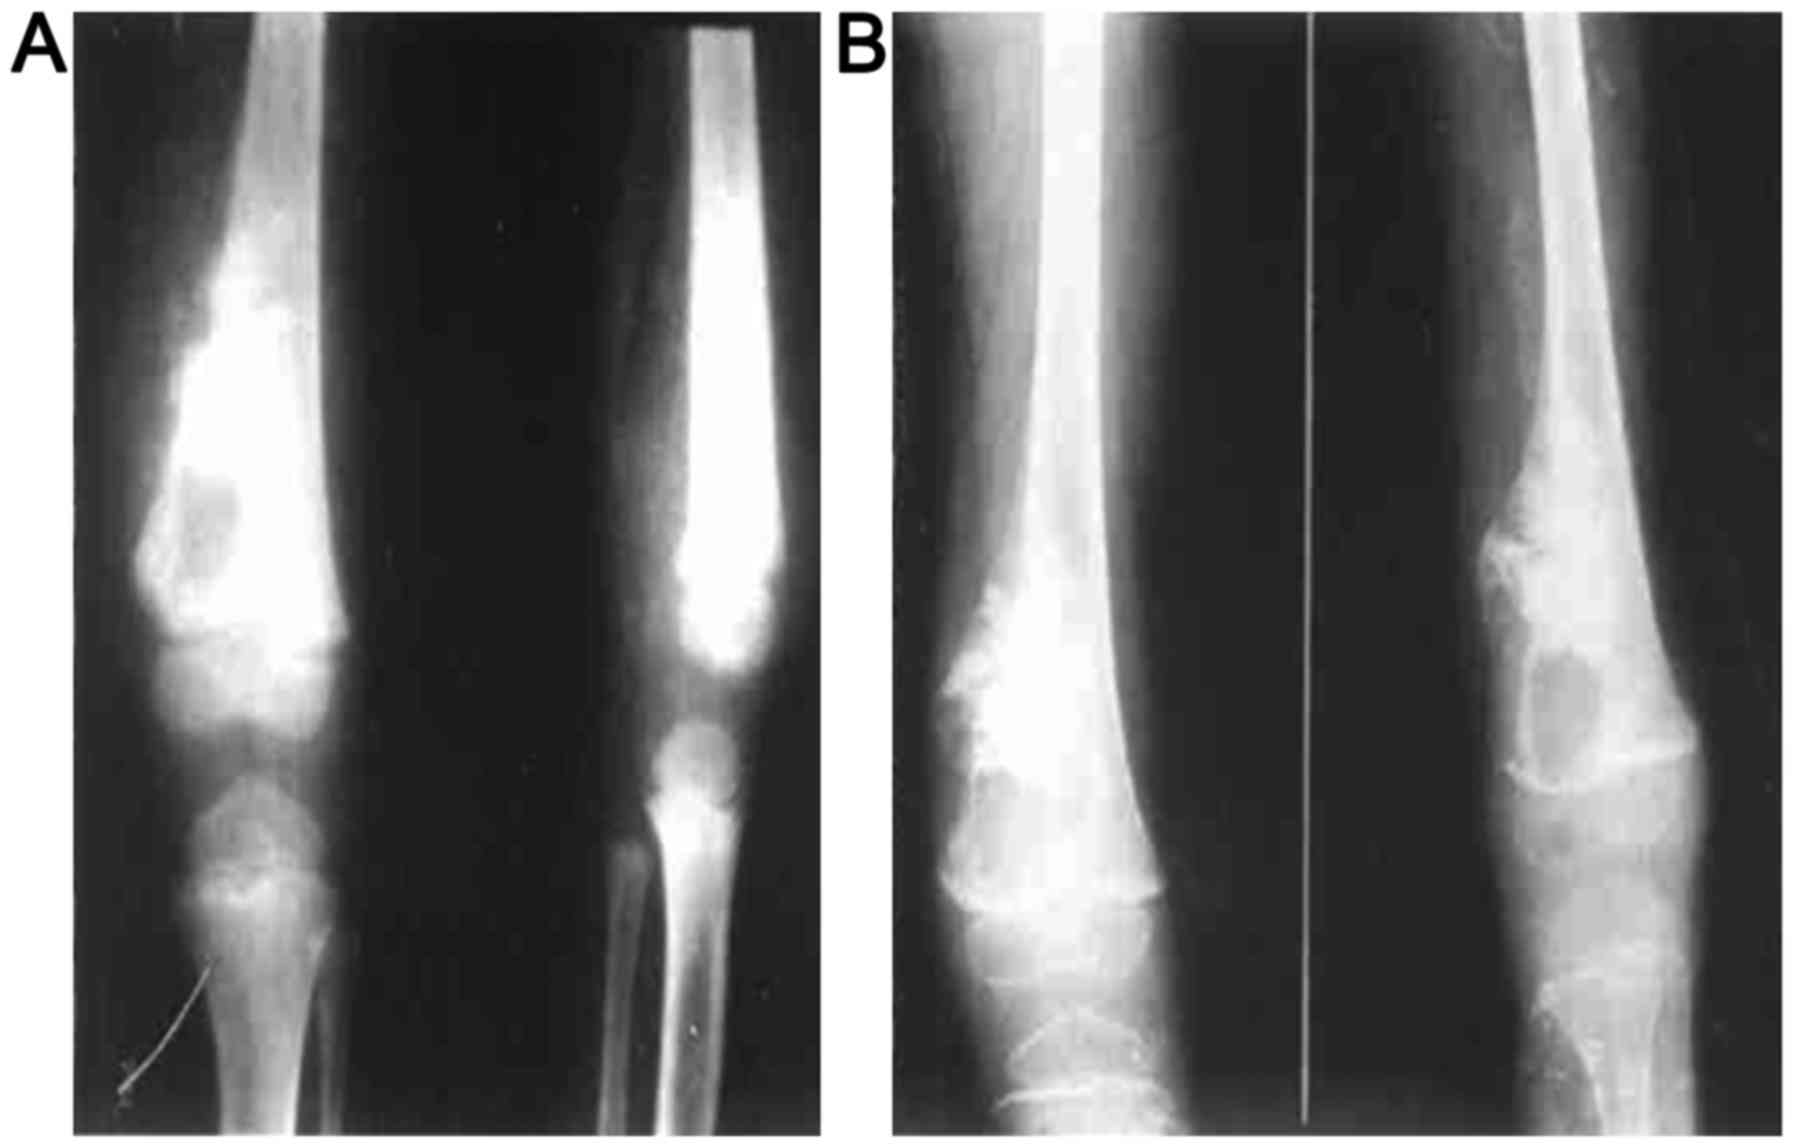

In this study, osteogenic changes were observed in

20 patients, osteoporosis in 6 cases, and a mixture of the two in 4

cases before chemotherapy. All patients exhibited typical

osteosarcoma osteolytic or sclerotic changes, with the tumor border

being unclear with cortical bone damage. An example of visible

changes to distal femoral osteosarcoma properties before and after

chemotherapy is shown in Fig. 1. An

example of visible changes to iliac osteosarcoma properties are

shown in Fig. 2.